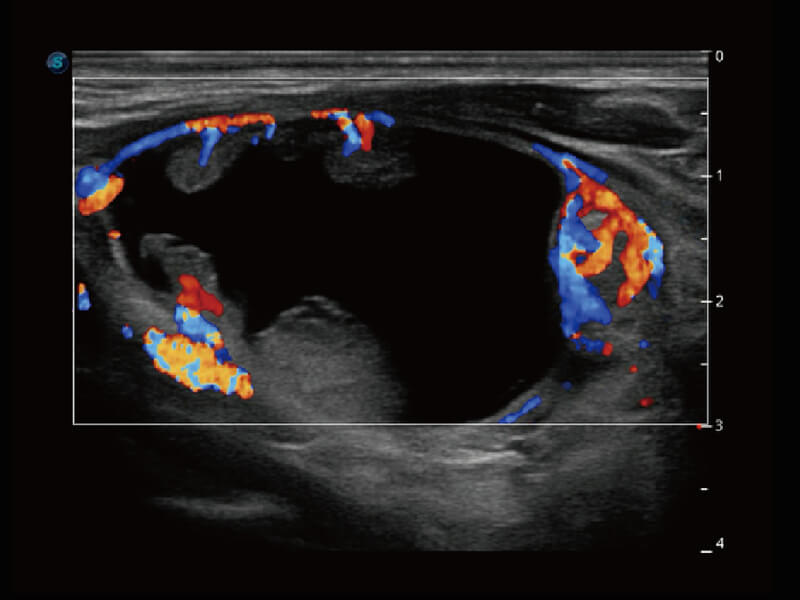

彩色多普勒超声诊断系统

S60探头工艺,从前端信号处理每一个环节采集无损声学数据,真实还原组织原貌,再现解剖细节。

超宽频带技术,为容积成像带来优质的二维图像基础,为您呈现丰富的结构细节,栩栩如生地展示宝宝的宫内形态以及各种组织的立体结构。